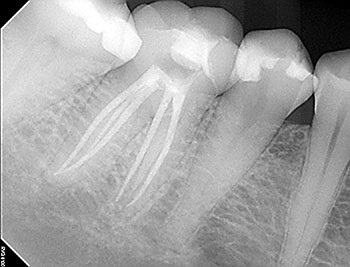

Case 10: Failing ‘well done’ NSRCT

This patient’s teeth #30 and #31 were treated by an endodontist. The endodontist found all the canals, achieved patency and shaped and filled each canal to length. When the periradicular tissues surrounding both teeth failed to heal, the endodontist recommended extracting both teeth because of VRFs. By then, tooth #31 developed a J-shaped lesion, suggestive of a VRF. Nothing suggested that tooth #30 had a VRF, other than that it was a “good-looking” or “well-done” NSRCT that failed. Yet both were recommended for extraction.

The somewhat skeptical patient came to see if these teeth really needed to be extracted. Nonsurgical retreatment was recommended. The patient didn’t want to lose his teeth, but he also didn’t want to pay to re-treat teeth that could not be saved.

Tooth #31—the tooth that was more likely to be fractured—was addressed first. To maximize the likelihood of healing, this tooth was treated in multiple visits using a calcium hydroxide intracanal medicament and obturated after bony healing was complete. The patient was delighted that his tooth had been saved, but also somewhat perplexed that the original endodontist gave up on a tooth that could have been saved. He has now scheduled re-treatment for tooth #30.

More than a few cases have been seen for second opinions after a dentist completed RCT on a tooth that failed shortly after, then told the patient to extract the tooth because it must be cracked because the NSRCT “looked perfect” radiographically. Although shaping and obturation can be judged radiographically, the most important factor—disinfection—cannot.

Endodontic Root Fracture Case Series

Fig.39: Preop CBCT.

Fig.40: Postop PA.

Fig.41: Recall PA.

Fig.42: Recall CBCT.